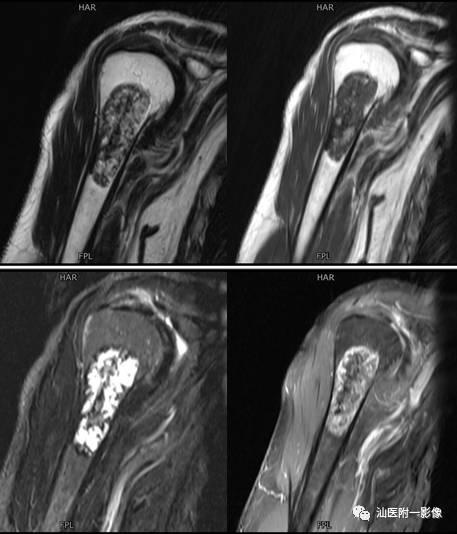

MR:

T2WI高信号的肿瘤软骨被低信号的纤维间隔分隔成不规则的分叶状,其内或边缘夹有更低信号钙化影T1WI:多为不均匀等低混杂信号。增强主要为纤维间隔强化,瘤软骨强化不明显。

•软骨母细胞瘤为来源于幼稚软骨细胞(软骨母细胞)。

•常见于青少年,多发生于10~20岁之间。

•多发生于四肢长骨,以胫骨、股骨和肱骨多见。

•软骨母细胞瘤的溶骨区常常开始位于骨骺,倾向于越过骨骺线,向干骺端蔓延。